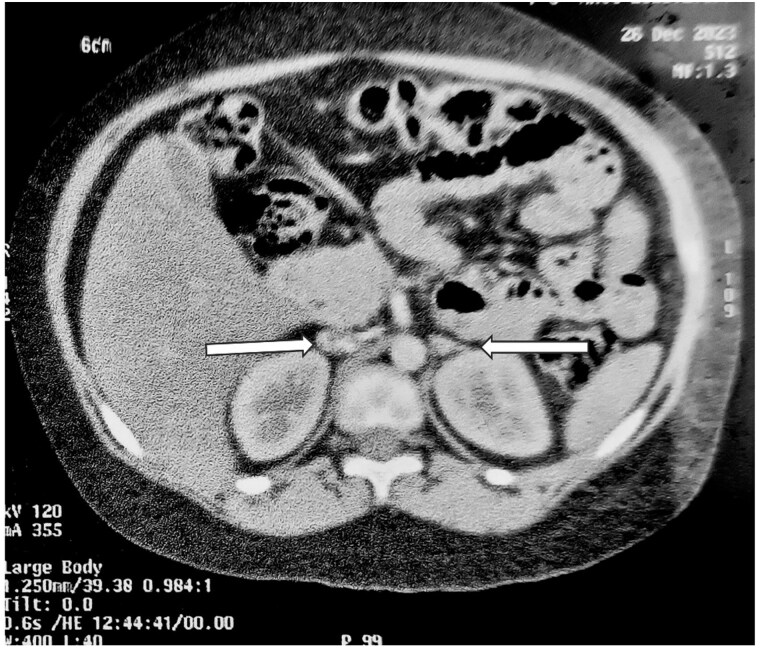

Primary pigmented nodular adrenocortical disease (PPNAD) is a rare but important cause of adrenocorticotropic hormone (ACTH)-independent Cushing syndrome (CS). It usually presents as cyclical CS in young adults. Childhood onset of PPNAD is exceedingly rare. About 90% of cases of PPNAD are associated with Carney complex (CNC). Both PPNAD and CNC are linked to diverse pathogenic variants of the PRKAR1A gene, which encodes the regulatory subunit type 1 alpha of protein kinase A (PKA). Pathogenic variants of PRKACA gene, which encodes the catalytic subunit alpha of PKA, are extremely rare in PPNAD. We report a case of a female child, aged 8 years and 3 months, who presented with features suggestive of CS, including obesity, short stature, hypertension, moon facies, acne, and facial plethora but without classical striae or signs of CNC. Hormonal evaluation confirmed ACTH-independent CS. However, abdominal imaging revealed normal adrenal morphology. Genetic analysis identified a duplication of the PRKACA gene on chromosome 19p, which is linked to PPNAD. The patient underwent bilateral laparoscopic adrenalectomy, and histopathological study confirmed the PPNAD diagnosis. Postoperative follow-up showed resolution of cushingoid features and hypertension. To our knowledge, this is the first reported case of a female child with PRKACA duplication presenting as CS due to PPNAD.